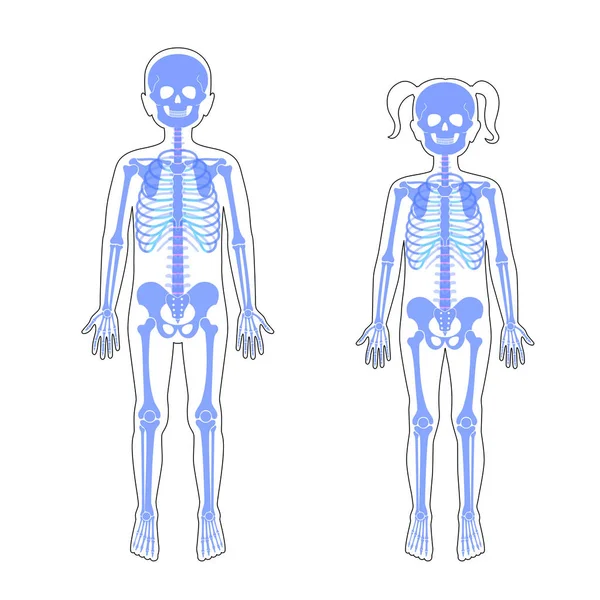

030517幼童骨骼圣身 030518男女童骨骼

030518男女童骨骼